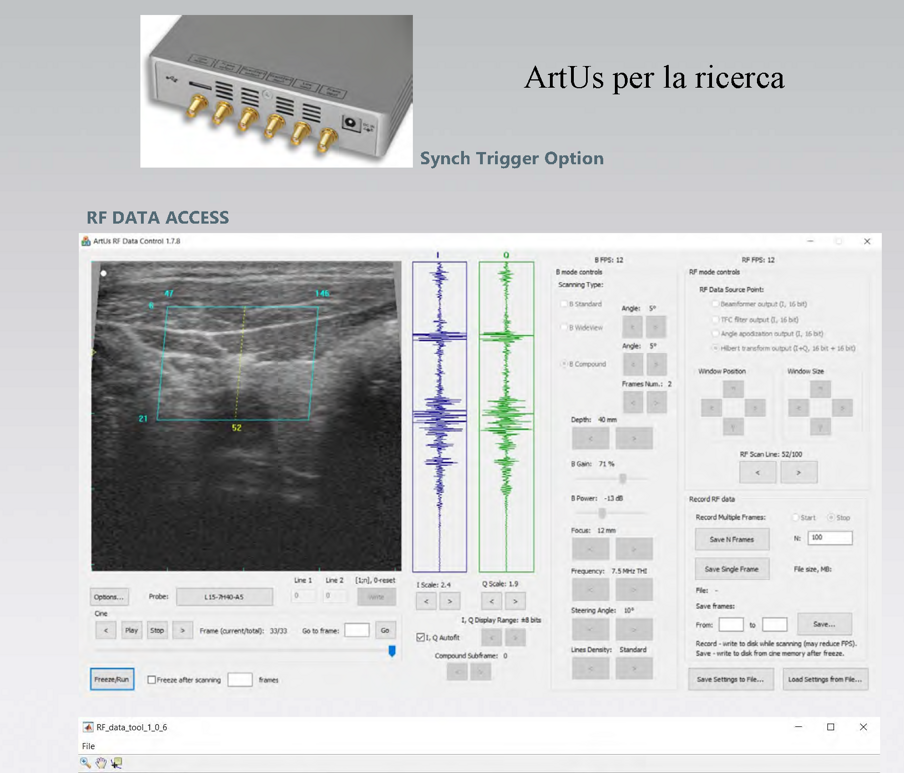

Sistemi diagnostici a ultrasuoni ad architettura aperta per la ricerca